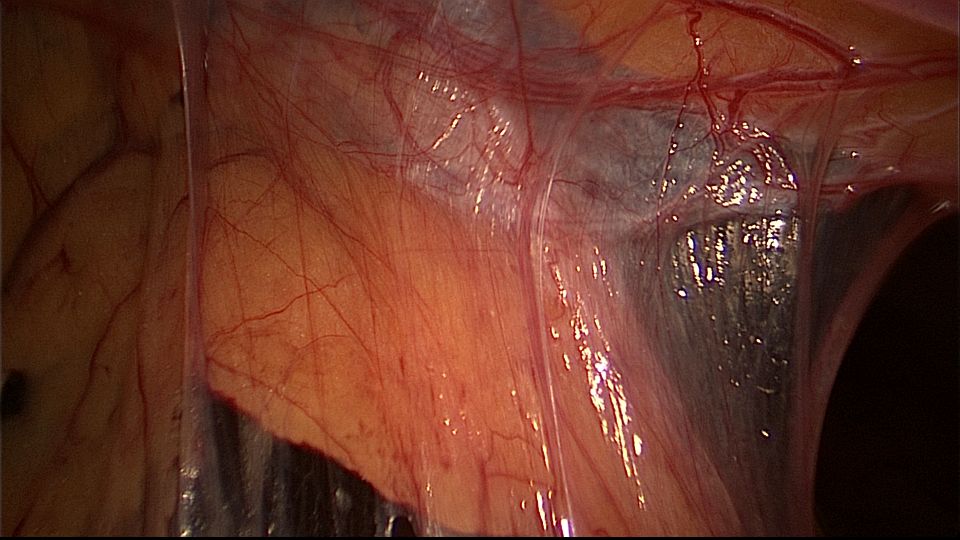

患者29岁,G1P0,继发不孕,2020年8月宫腹腔镜探查,大网膜与腹前壁多处粘连,子宫后壁与直肠前壁广泛粘连,宫腔中央型宽大柱状粘连,宫腔两侧少许粘连。电钩分离盆腔粘连,冷刀分离宫腔粘连,恢复宫腔形态,显露双侧输卵管开口,术中美兰通夜,双侧输卵管通畅。2020年10月宫腔镜二探取球囊,宫腔形态正常,双侧输卵管开口可见。2021年3月自然妊娠,外院足月分娩。现34岁,G2P1。